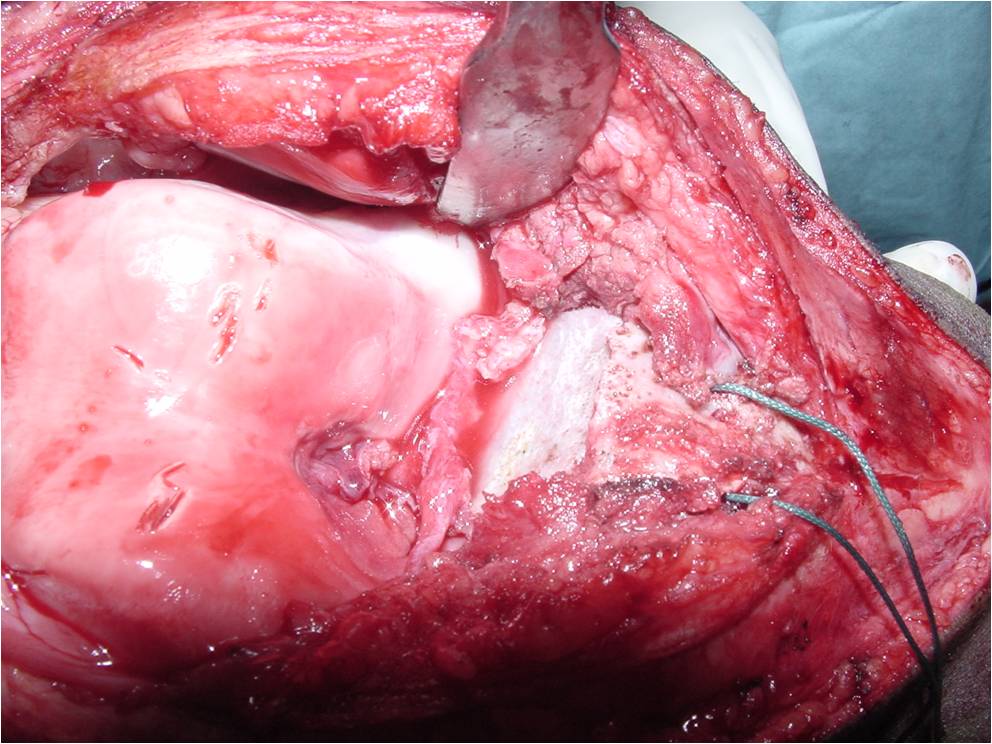

Treatment of a Chondroblastoma of Proximal Humerus with Intralesional Curettage Resection, Cryosurgery and Bone Grafting

- intralesional curettage resection and bone grafting most common treatment

- Cement and internal fixation may also be used to fill the defect after removal for selected patients

- Local adjuvants such as cryosurgery (liquid nitrogen application) may be considered to decrease the risk of local recurrence

Gross Pathology

- Grossly variable appearance

- Grey/yellow/brown and gritty if has interspersed calcifications

- Interspersed red areas from hemorrhagic necrosis

- May be blue-grey areas from the chondroid matrix

- Rim of sclerotic bone is visible in totally resected specimens